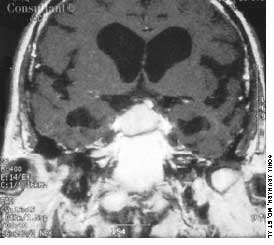

A 75-year-old woman with a bioprosthetic aortic valve, who had undergone surgical repair of an aortic root aneurysm 9 months earlier was hospitalized with fever, headache, and altered mental status of 1-day's duration.